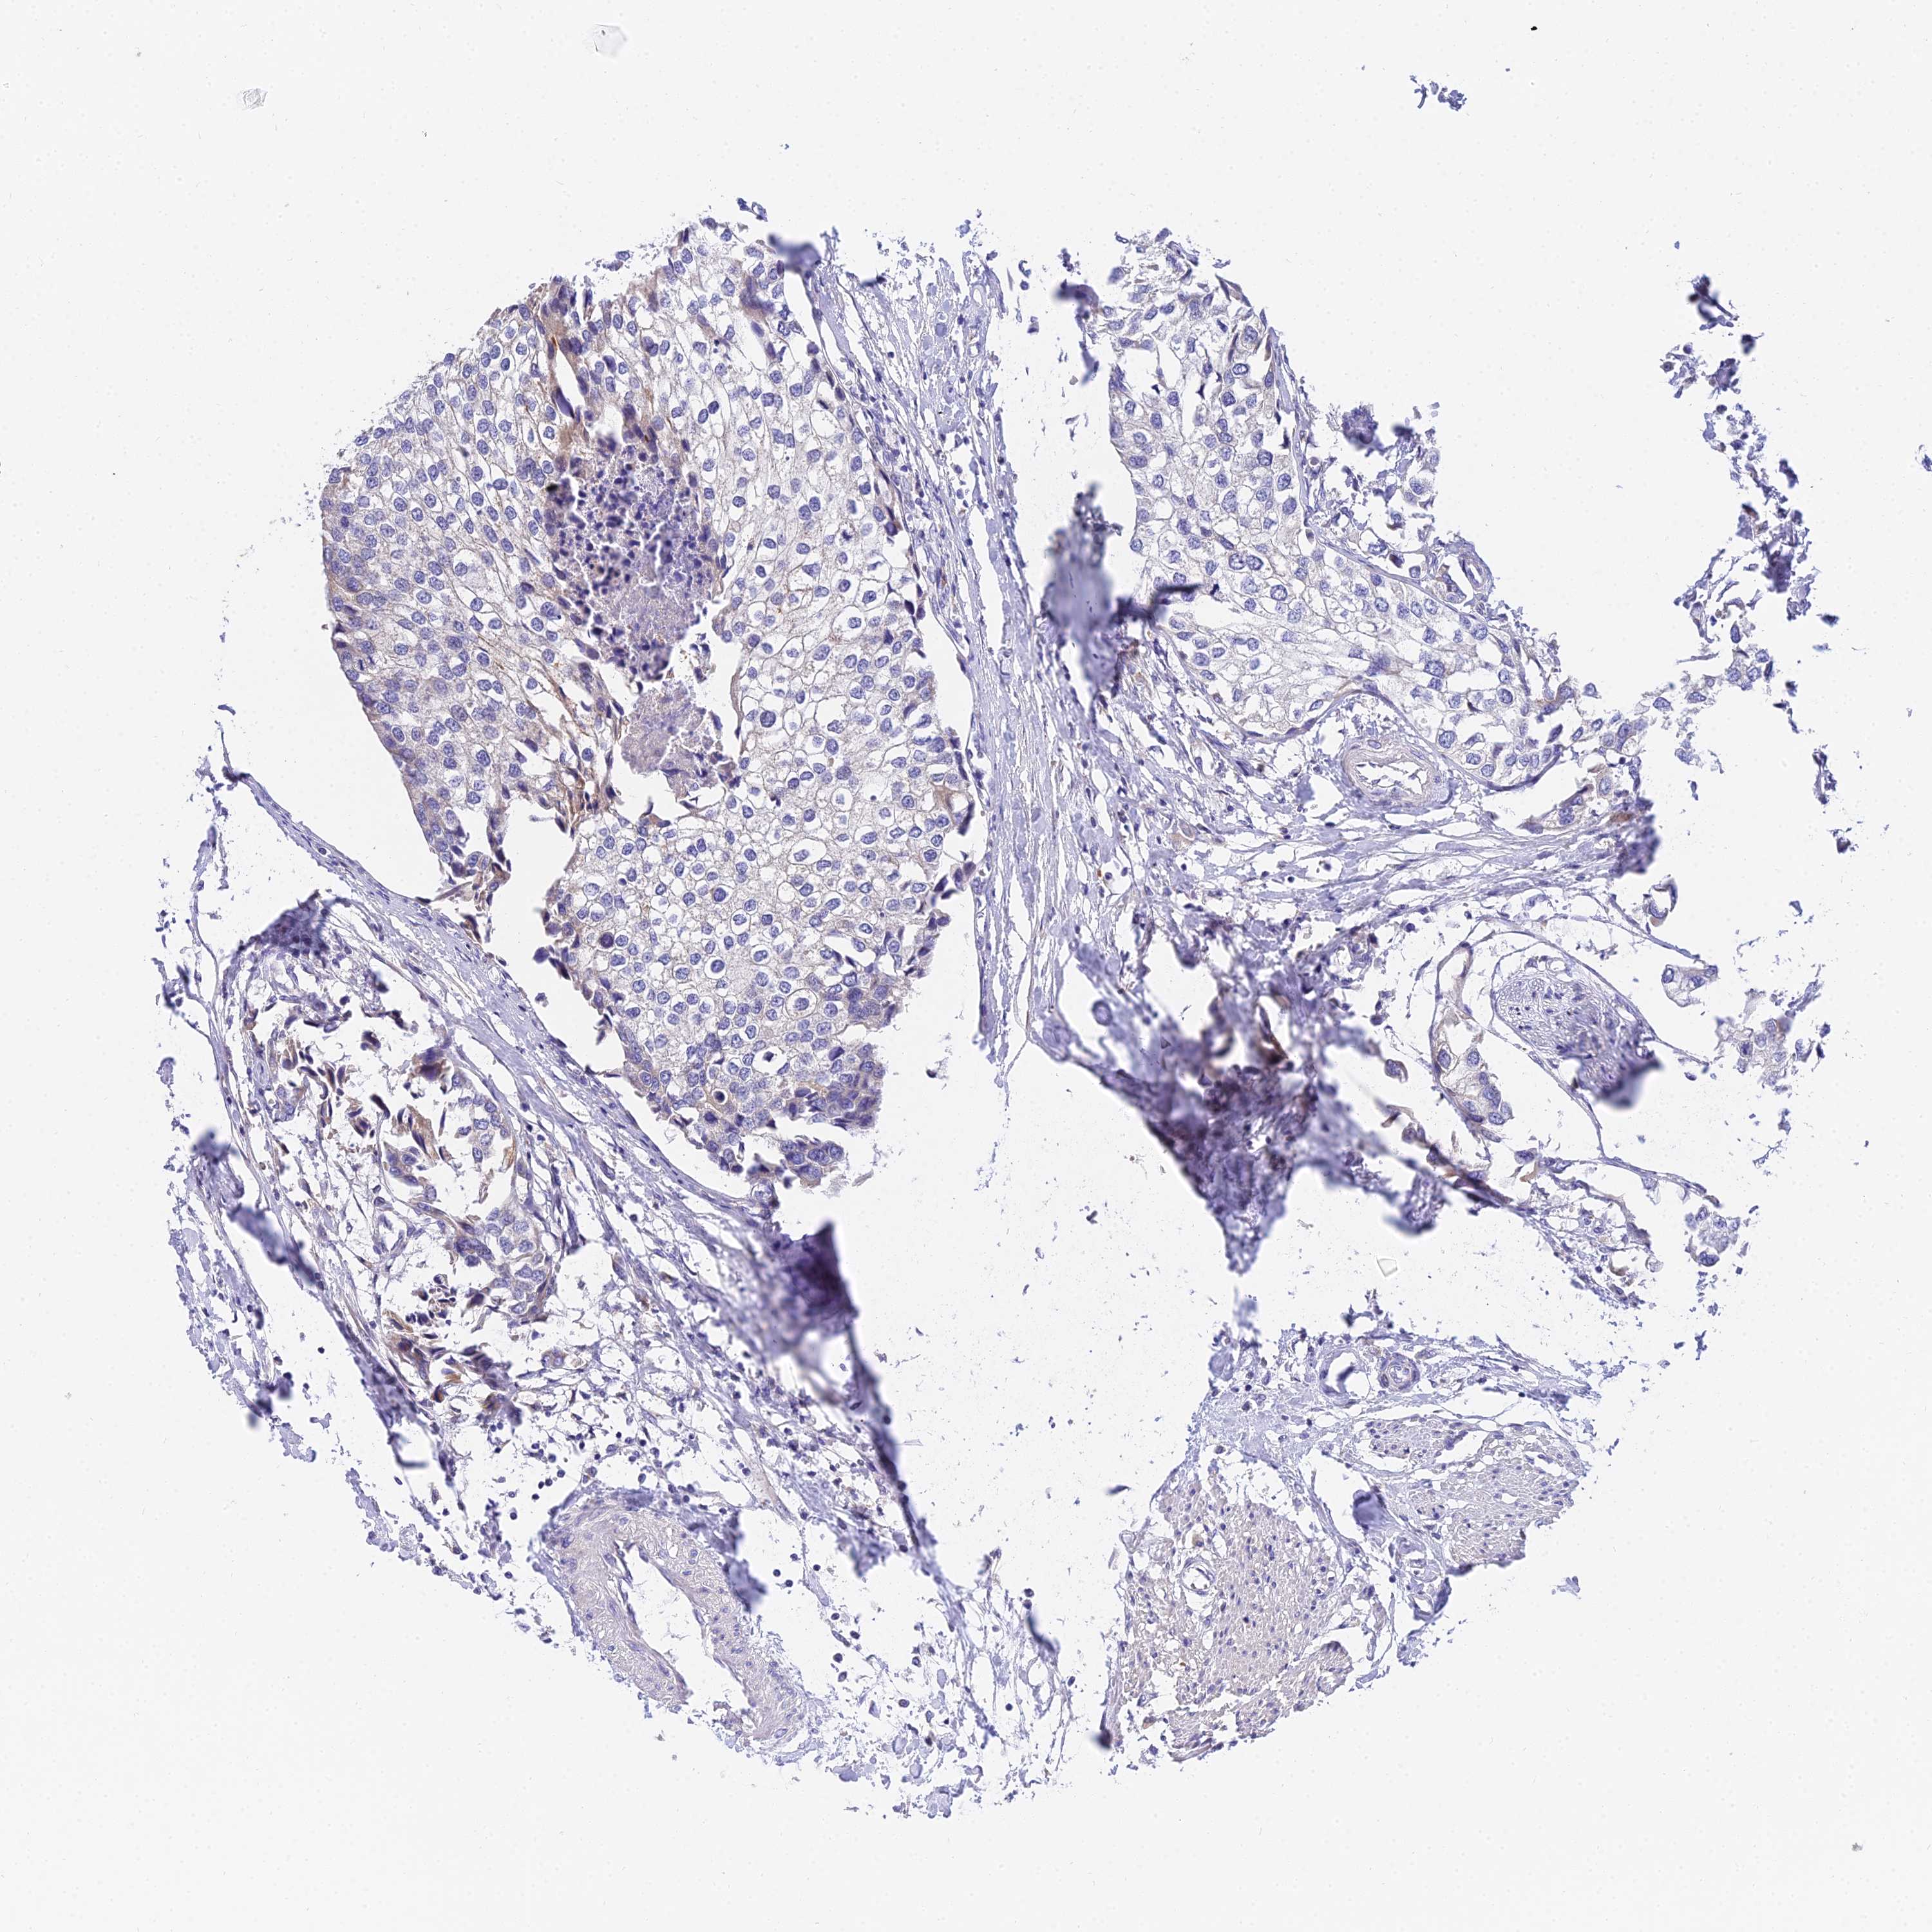

UROTHELIAL CANCER - Protein expressioni

A mouse-over function shows sample information and annotation data. Click on an image to view it in a full screen mode. Samples can be filtered based on level of antibody staining by selecting one or several of the following categories: high, medium, low and not detected. The assay and annotation is described here.

Note that samples used for immunohistochemistry by the Human Protein Atlas do not correspond to samples in the TCGA dataset.

Antibody stainingi

Antibody staining in the annotated cell types in the current human tissue is reported as not detected, low, medium, or high, based on conventional immunohistochemistry profiling in selected tissues. This score is based on the combination of the staining intensity and fraction of stained cells.

Each image is clickable and will lead to virtual microscopy that enables deeper exploration of all samples and also displays staining intensity scores, fraction scores and subcellular localization as well as patient and tissue information for each sample.

Antibody HPA038759

Antibody HPA040515

Antibody HPA045924

Urothelial carcinoma, High grade

Urothelial carcinoma, Low grade